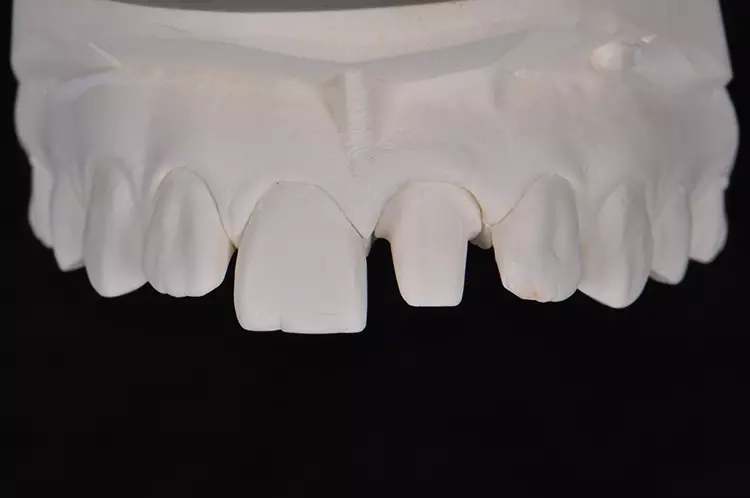

Die Auswahl des Materials für die definitive Krone wurde in Rücksprache mit dem Zahntechniker getroffen. Sie erfolgte nach der Herstellung der Arbeitsmodelle, der Beurteilung der Platzverhältnisse, der Stumpffarbe und der definierten Zielfarbe. Aufgrund des verfärbten und devitalen Zahnes und zur Vermeidung des „Grauschleiers“ galt es, ein Material mit weniger Transluzenz als Lithiumdisilikat zu verwenden.

Es sollte ein Zirkonoxidmaterial mit hochästhetischen Eigenschaften zum Einsatz kommen. Die Wahl fiel auf IPS e.max ZirCAD Prime, ein Werkstoff der zwei Zirkoniumdioxid-Rohstoffe kombiniert: im Dentinbereich ein 3Y-TZP-Zirkonia mit hoher Festigkeit (1.200 MPa Biegefestigkeit) und im Schneidebereich ein transluzenteres 5Y-TZP-Zirkonia (650 MPa Biegefestigkeit). Der stufenlose Farb- und Transluzenzverlauf in den Materialscheiben ist ein zusätzlicher Vorteil für derartige Restaurationen im sichtbaren Bereich.

Das Ausarbeiten von Details und die minimale Reduktion der Labialfläche für das Microveneering erfolgt grundsätzlich im weichen, kreideartigen Weißzustand. Das so bearbeitete und modifizierte Gerüst wird nun bei 1.530 °C gesintert und schrumpft dabei volumenmäßig um ca. 25% zum eigentlichen hochfesten Zirkonoxidgerüst.

Zur Realisierung eines möglichst naturgetreuen Behandlungsergebnisses wurde labial ein minimales Cut-back und eine anschließende individuelle Schichtung mit der Verblendkeramik IPS e.max Ceram durchgeführt (Mikroveneering) (Abb. 30–33). Damit der verfärbte Zahnstumpf unter der neuen Zirkonkrone nicht mehr sichtbar ist, wird bei transluzentem Zirkoniumdioxid im Weißzustand auf der Innenseite des Gerüstes ein Opakerliquid aufgebracht. Dieses Liquid trägt nicht auf, da das Material in den Werkstoff eindringt und das Zirkongerüst an den gewünschten Stellen von innen blickdicht, sprich opak, wirken lässt (Fa. BriegelDental) (Abb. 34 und 35).